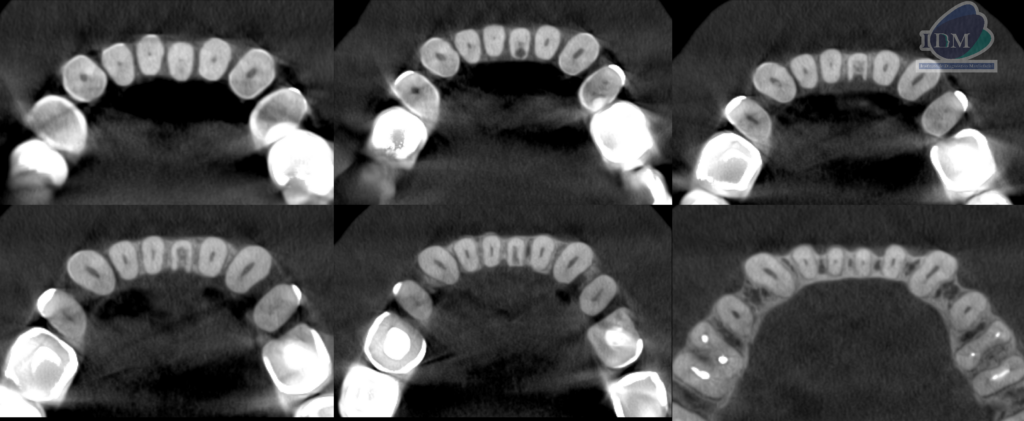

A la evaluación de la tomografía computarizada cone beam de campo mediano se observa en los cortes axiales, transaxialres y tangenciales la presencia de una imagen hipodensa que se localiza a nivel de tercio cervical de la pieza 31 por debajo del límite amelocementario en la superficie lingual la cual se comunica con el conducto pulpar ocasionando la alteración en su morfología, finalmente se observa un discreto ensanchamiento del espacio para el ligamento periodontal apical, compatible con reabsorción cervical invasiva (RCI)

CORTES AXIALES